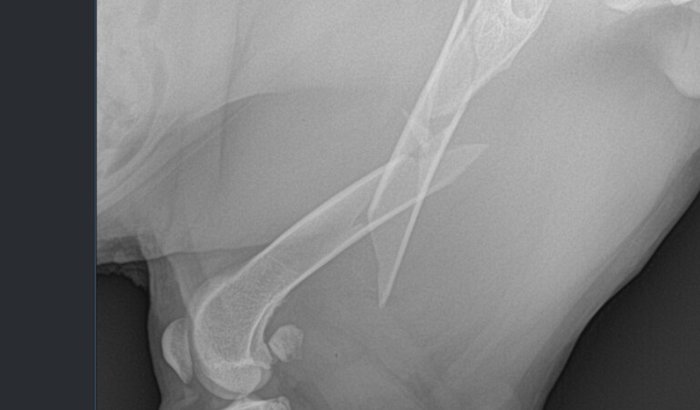

No dia 11/12/2025, porém, nossa querida Cigana foi atropelada e fraturou o fêmur. Para que ela volte a correr e brincar sem dor, é fundamental realizar a cirurgia, que custa R$ 3.250,00, além da medicação pós-operatória.